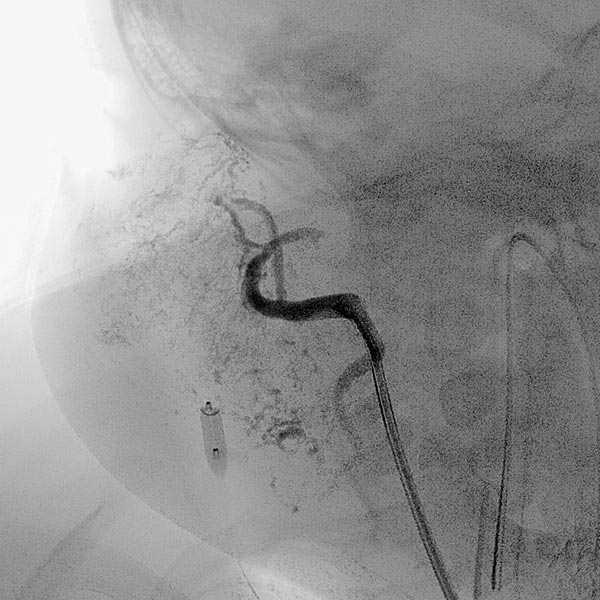

Digitale Subtraktionsangiographie (DSA): Nach Einbringen transarteriell eines Führungskatheters 4F in die Arteria carotis externa und Vorbringen eines Mikrokatheters in die Arteria maxillaris. Das Hämangiom zeigt sich als typisches KM-Pooling (Tumorblush). Gut zu sehen auch der transvenös eingebrachte Ballon, der den venösen Abstrom ausblockt. Hier wird jetzt mit Partikeln der Größe 150 Mikron embolisiert ohne dass diese Partikel venös abströmen können.

Digitale Subtraktionsangiographie (DSA) nach erster Embolisation mit Partikeln. Ein Teil des Hämangioms ist schon ausgeschaltet.